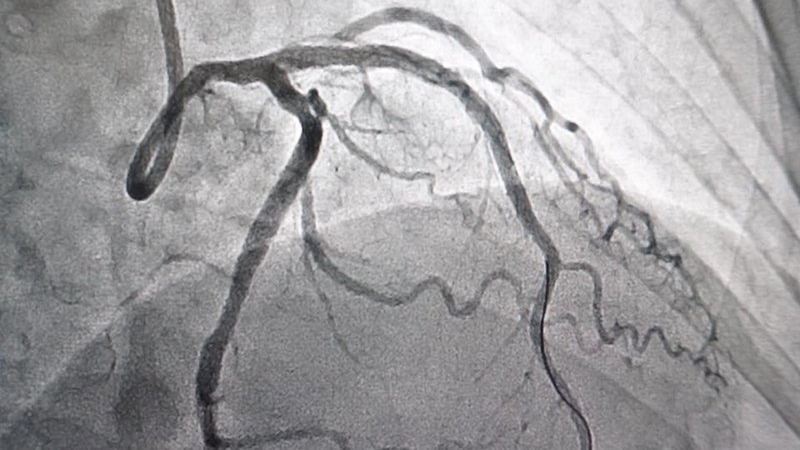

Chụp DSA hay còn được biết đến với tên gọi chụp mạch máu kỹ thuật số hóa xóa nền là một phương pháp chẩn đoán hình ảnh tiên tiến được sử dụng để đánh giá chi tiết các mạch máu trong cơ thể. Phương pháp này sử dụng một loại cản quang đặc biệt được tiêm vào các động mạch, sau đó các bức ảnh chụp X-quang sẽ được thực hiện.

Bằng cách sử dụng phần mềm máy tính, hình ảnh nền sẽ được lấy đi, chỉ để lại hình ảnh của các mạch máu đã được nhuộm màu. Điều này cho phép các bác sĩ chẩn đoán một cách chính xác các bệnh lý như tắc nghẽn, hẹp mạch, hay xuất huyết mà không bị ảnh hưởng bởi các cấu trúc xung quanh.

Thông qua kỹ thuật này, các bác sĩ có thể có được hình ảnh chi tiết và rõ ràng về hệ thống mạch máu, giúp phát hiện sớm và chính xác các vấn đề như tắc nghẽn, phình mạch, hay dị dạng động - tĩnh mạch.

Chụp DSA có khả năng cung cấp hình ảnh chất lượng cao với độ phân giải vượt trội, cho phép các bác sĩ thấy được những thay đổi nhỏ nhất trong cấu trúc mạch máu. Điều này đặc biệt quan trọng trong việc chẩn đoán và lên kế hoạch can thiệp cho các bệnh nhân mắc phải các bệnh lý phức tạp ở não, cổ, ngực và các chi.